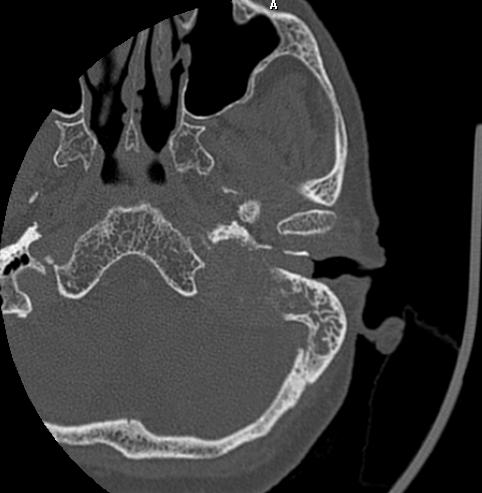

1.CT平扫呈等或略高密度,颈静脉孔扩大,邻近骨质破坏。肿瘤经颈静脉孔入颅生长时,可累及桥小脑角、中耳、脑干和第四脑室,肿瘤累及乙状窦并不少见;向颅外生长可进入颈部咽旁间隙。增强后扫描病灶呈均匀明显强化。

左颈静脉孔可见一个明显强化病灶,大小约为3.5 x 3.5 x 3.5 cm。病变导致颈静脉孔破坏和扩大。

在内侧,病变在后颅窝有颅内硬膜外延伸,使小脑皮质凹陷。

在外侧,病变延伸到中耳腔(上鼓室、中鼓室和下鼓室)和外耳道。砧骨长突、下半规管、耳蜗底回和面神经鼓室段外侧壁均有侵蚀。

病变浸润颈静脉球,并向近端颈静脉延伸。在后方,枕骨基底部和枕骨大孔的外侧被破坏。